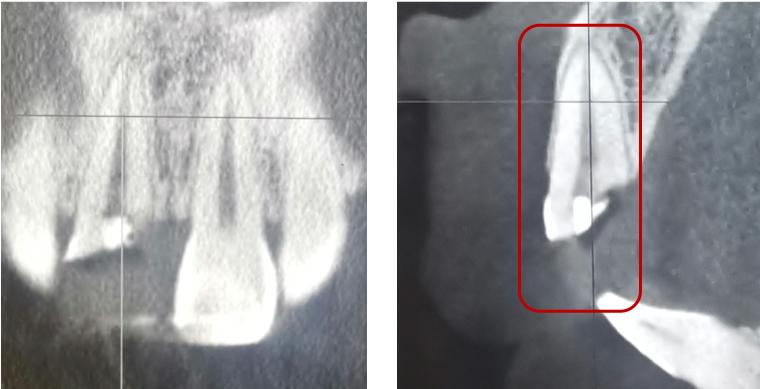

根折--根颈1/3

治疗方案:复位松动移位的牙冠,夹板固定4周,折断线近牙颈部固定时间延至4个月,定期检测折断线愈合情况,监测牙髓状态。牙髓坏死或感染则进行冠方的牙髓治疗。如颈部折断后断片异常松动,治疗则同冠根折。